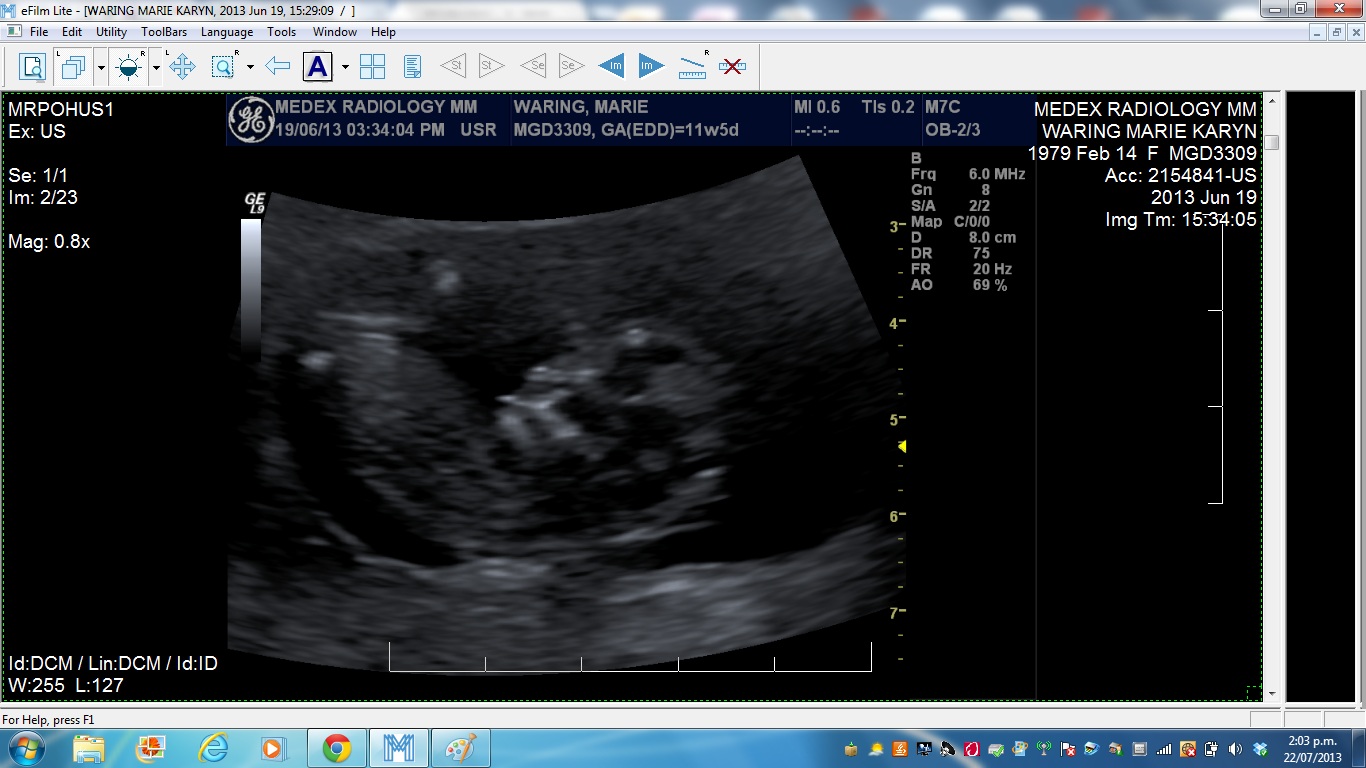

Attachment 12493

leaning boy off your last pic.

Yeah, new pic leans me more blue :)